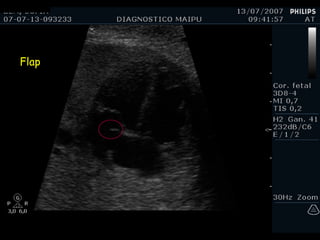

Flap